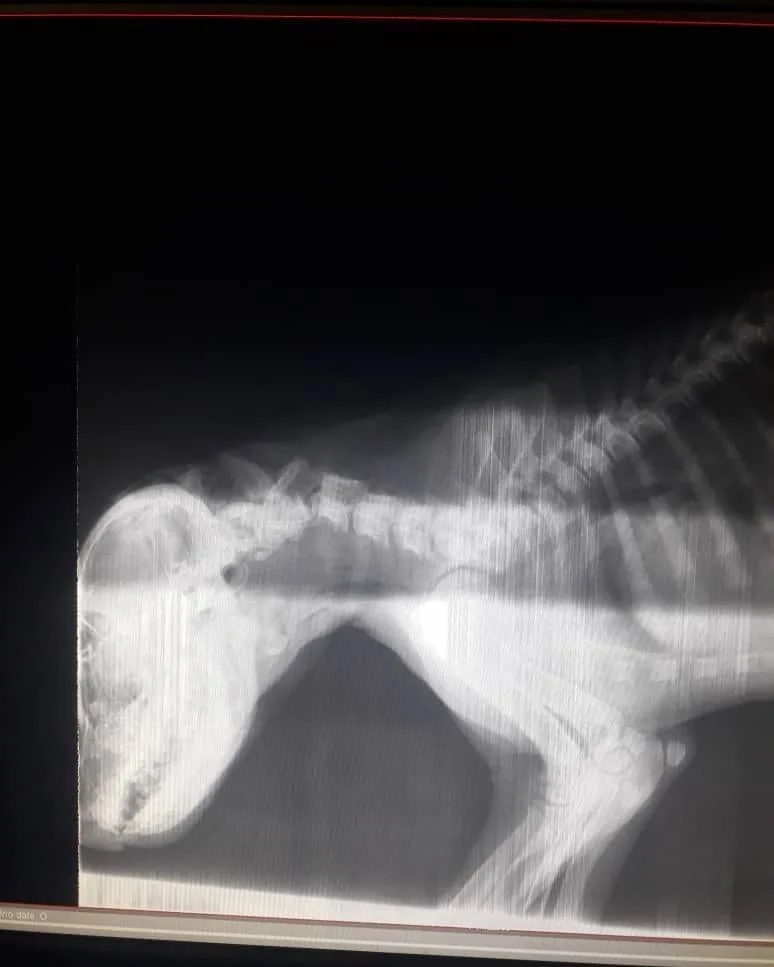

At the clinic, his condition was critical. The cervical vertebrae in his neck were fractured, leaving him in excruciating pain. Many debated euthanasia, fearing that survival was impossible and that keeping him alive would only prolong his suffering.

But the team chose hope. A skilled surgeon undertook an hours-long operation, carefully stabilizing his spine with plates and precision. It was a race against time, and against despair.